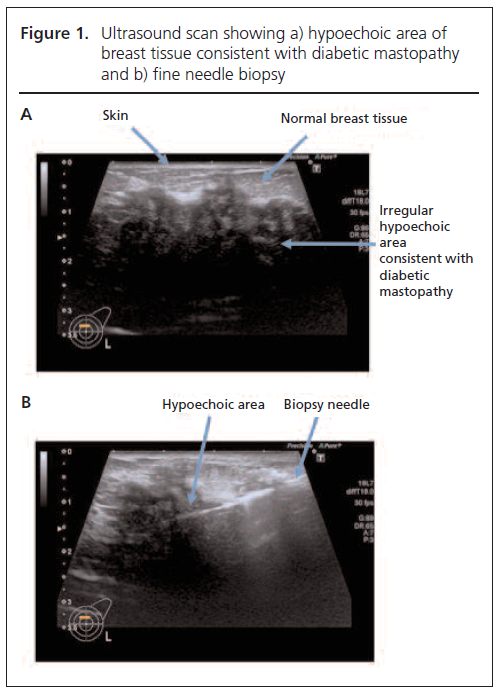

On clinical examination she had a tender, mobile, irregular 5 cm mass in her left breast. There was no associated nipple discharge, skin or breast changes, and no lymphadenopathy. In view of this suspicious breast lump, further radiological investigations were arranged. An ultrasound scan demonstrated an ill-defined hypoechoic mass (Figure 1A). Core biopsies containing breast tissue with dense fibrosis were obtained (Figure 1B). Histological examination revealed no evidence of ductal carcinoma in situ or invasive malignancy; however, there were areas of focal perivascular chronic inflammation in keeping with a diagnosis of DMP (Figure 2).

Mammography of DMP shows diffuse dense glandular tissue, but current imaging techniques are unable to distinguish between mastopathy and malignancy. An ultrasound-guided fine needle aspiration or core biopsy to demonstrate the characteristic histology remains the investigation of choice. Histological features include lymphocytic lobulitis, ductitis and perivasculitis with stromal keloid fibrosis. Histological criteria for the diagnosis of DMP, as defined by Siedman et al,7 include: (1) collagenous stroma with keloid-like features and an increased concentration of spindle cells; and (2) mature lymphocytes clustered around small blood vessels, lobules and ducts.